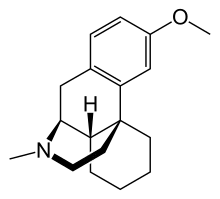

Morphinans

Morphinan series

- N-Methylmorphinan

Structures

N-Methylmorphinan N-Methylmorphinan |